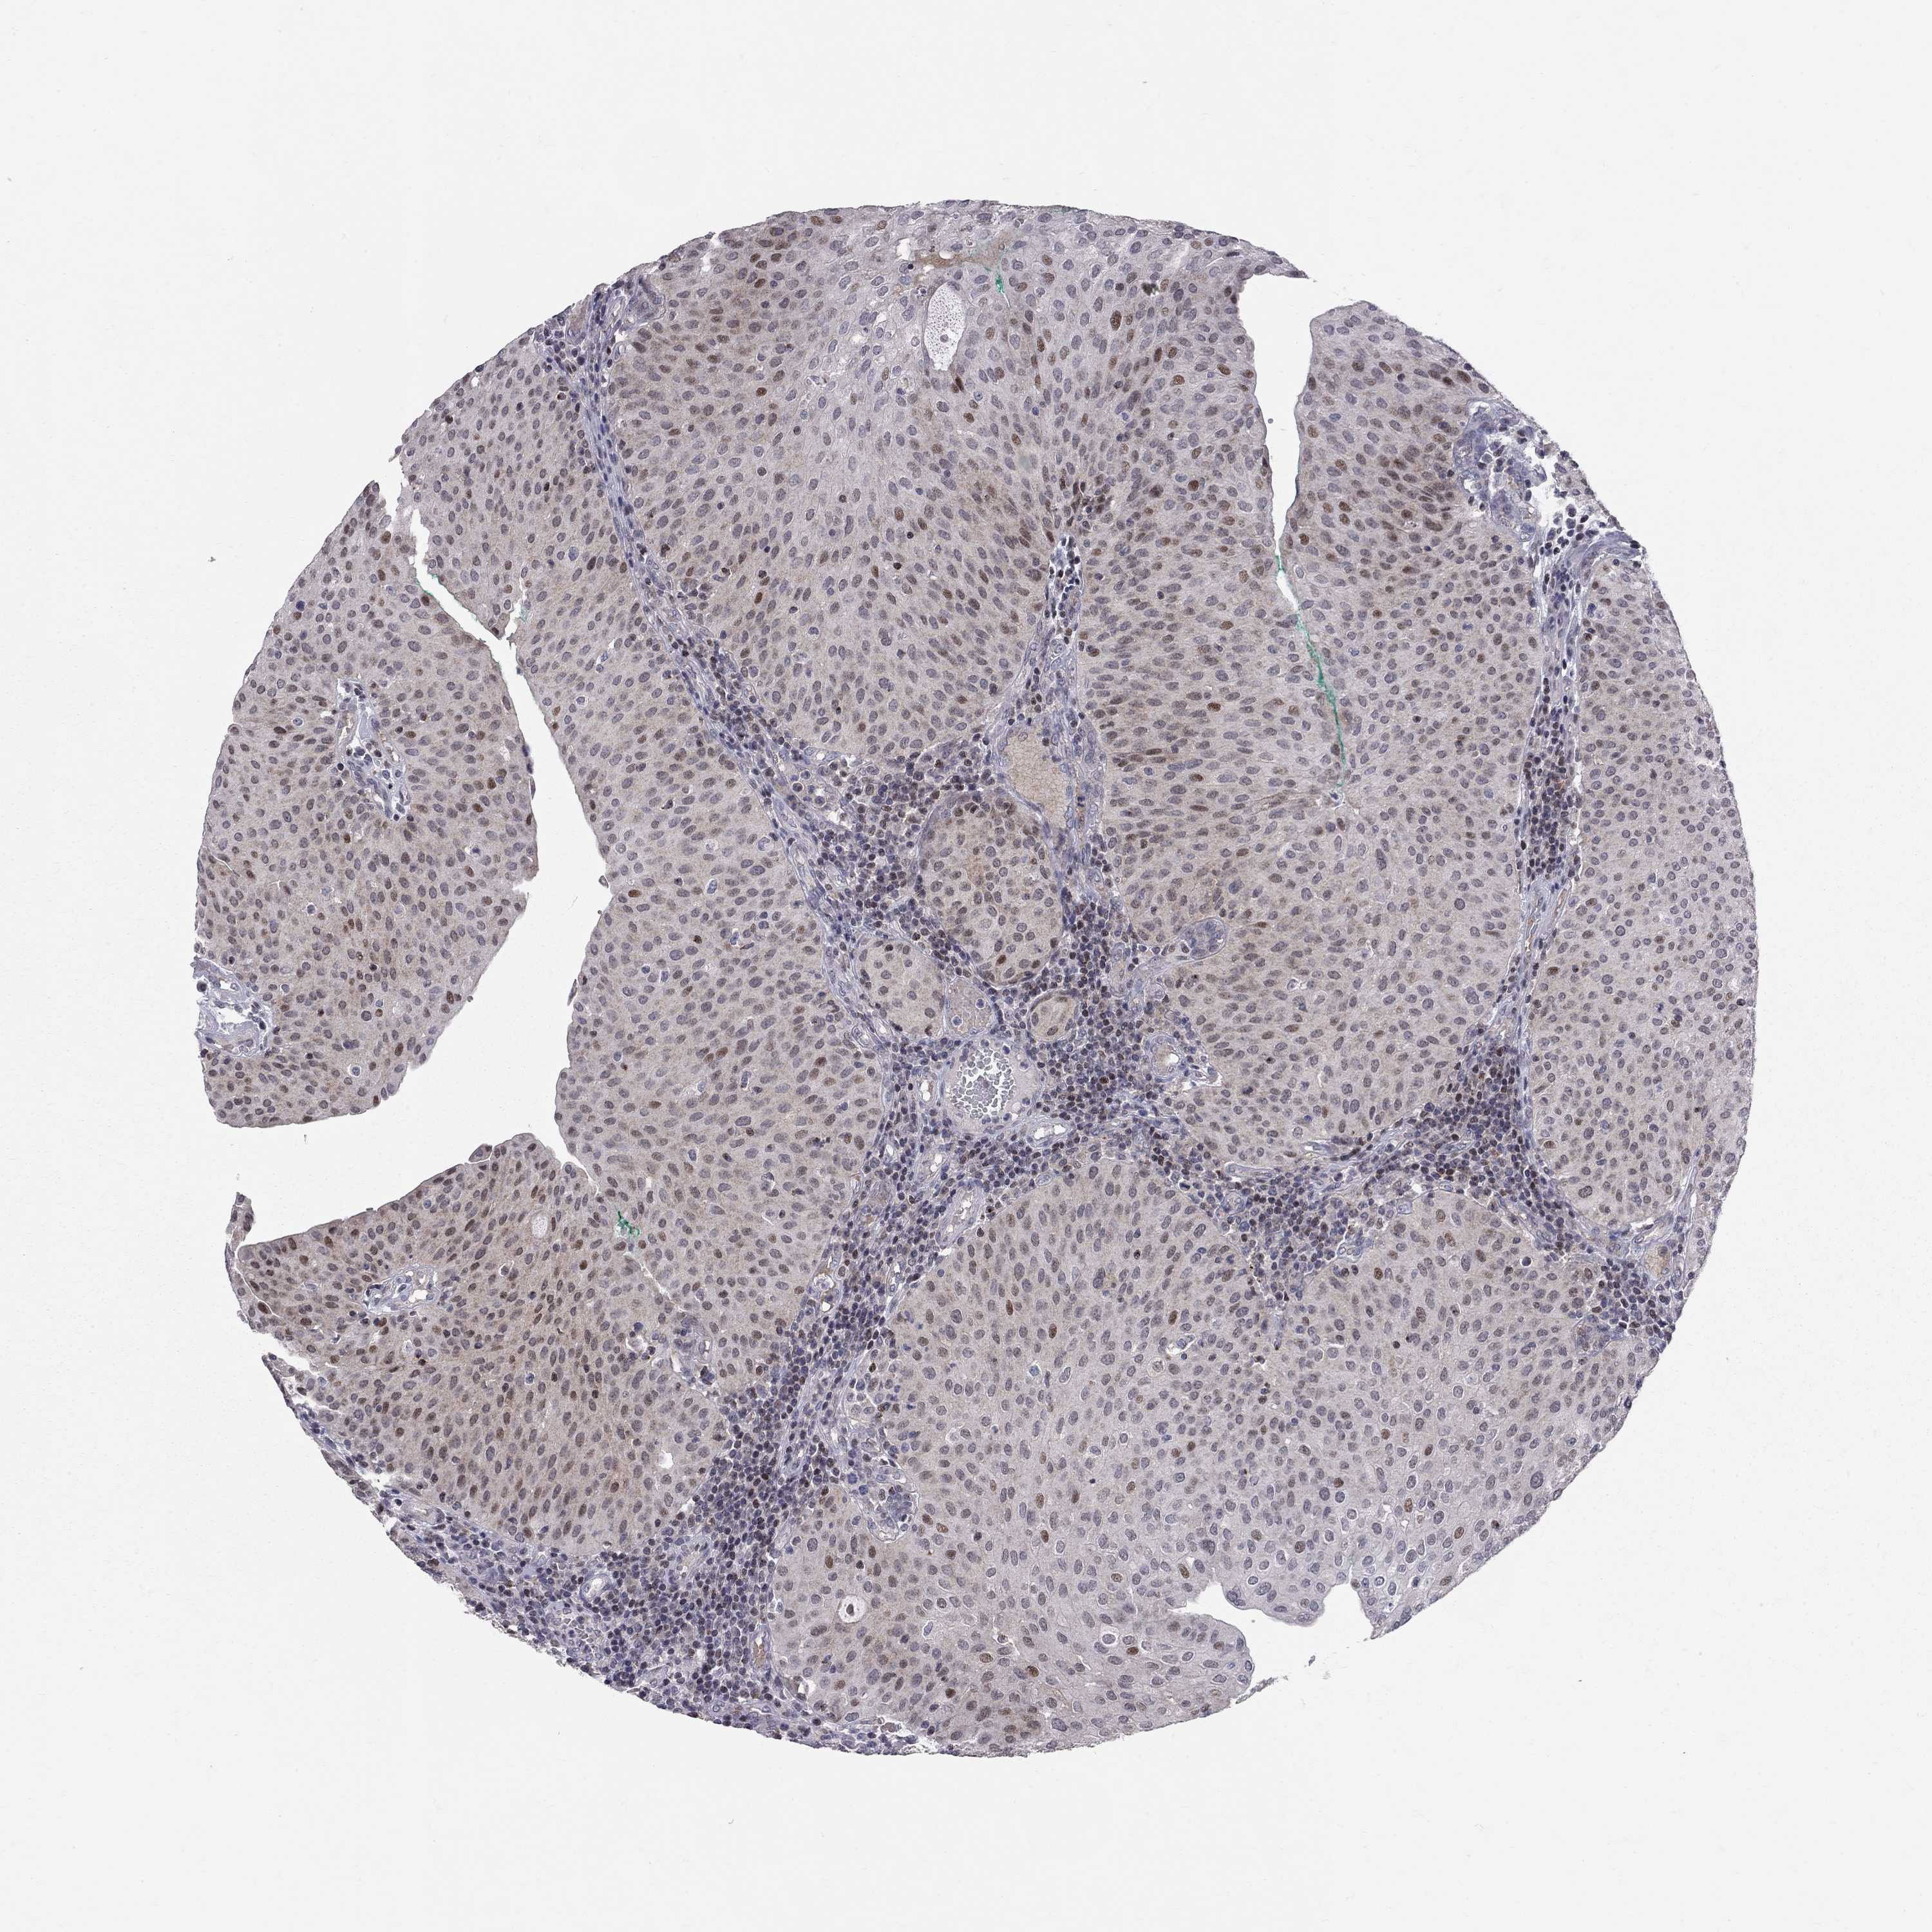

UROTHELIAL CANCER - Protein expressioni

A mouse-over function shows sample information and annotation data. Click on an image to view it in a full screen mode. Samples can be filtered based on level of antibody staining by selecting one or several of the following categories: high, medium, low and not detected. The assay and annotation is described here.

Note that samples used for immunohistochemistry by the Human Protein Atlas do not correspond to samples in the TCGA dataset.

Antibody stainingi

Antibody staining in the annotated cell types in the current human tissue is reported as not detected, low, medium, or high, based on conventional immunohistochemistry profiling in selected tissues. This score is based on the combination of the staining intensity and fraction of stained cells.

Each image is clickable and will lead to virtual microscopy that enables deeper exploration of all samples and also displays staining intensity scores, fraction scores and subcellular localization as well as patient and tissue information for each sample.

Antibody HPA052052

Antibody CAB005583

Antibody CAB072336

Urothelial carcinoma, High grade

Urothelial carcinoma, Low grade

Urothelial carcinoma, NOS